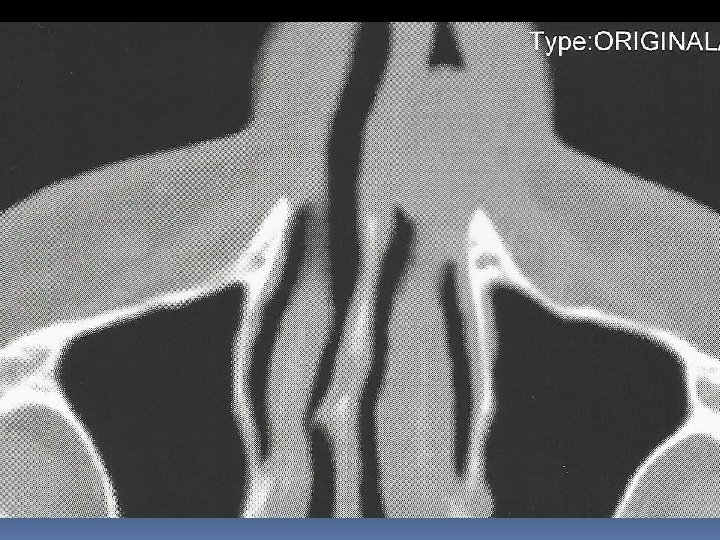

Case Report Paziente di sesso maschile, a. 58, in buona salute Ostruzione nasale omolaterale Neoformazione polipoide carnosa con mucosa integra che occlude anteriormente la fossa nasale sinistra

Intervento chirurgico: asportazione della neoformazione impiantata sulla testa del turbinato inf. in blocco con testa, corpo e parte della coda del turbinato, i margini di resezione appaiono macroscopicamente indenni

Referto istopatologico Neoformazione polipoide impiantata sulla testa del turbinato inferiore, diametro cm. 1 x 2, al taglio appare di colorito biancastro, solida e consistente. Reperti istologici ed immunoistochimici compatobili con melanoma della mucosa della fossa nasale, negativi i limiti di resezione. Sono state eseguite colorazioni con S 100, MART – 1 e HMB 45. Indice di proliferazione 3%